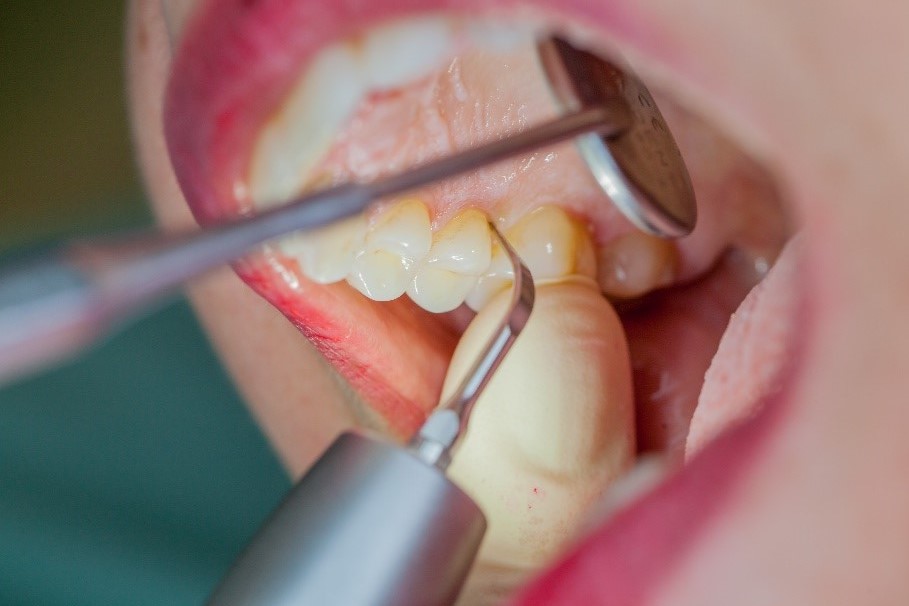

Si nécessaire, un traitement parodontal préventif est effectué. Un nettoyage dentaire professionnel contribue dans un premier temps à des conditions gingivales saines. Il permet d’éliminer le tartre (Fig. 1) et le biofilm (Fig. 2) jusque dans le sulcus gingival. En association à des consignes d’hygiène buccodentaire méticuleuses,

il élimine également à long terme le risque de récidives d'inflammation chez le patient.[15]